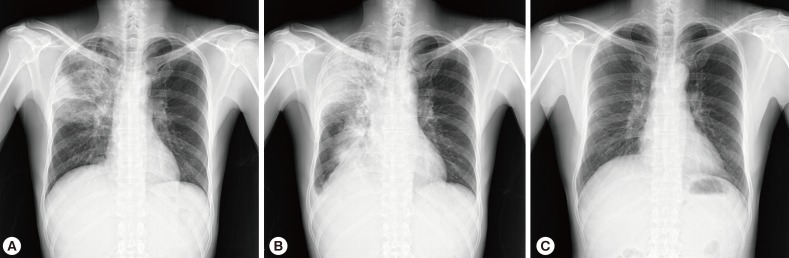

Chest X-ray and computed tomography (CT) showed large consolidations in the right upper lobe, middle lobe, and lower lobe superior segments (

Fig. 1A,

After percutaneous lung biopsy, voriconazole (4 mg/kg, intravenous every 12 hr) was given to the patient on the 9th day of hospitalization due to concerns regarding resistance to amphotericin B. However, despite voriconazole treatment, the patient complained of dry cough with persistent fever, and the size of the right-side pleural effusion increased (

Fig. 1B). A pleural effusion assay showed eosinophil-dominant exudates with a protein of 4,600 mg/dl, lactate dehydrogenase (LDH) of 643 U/L, adenosine deaminase (ADA) of 13.6 U/L, and a whole blood cell (WBC) count of 1,400/µl (eosinophils 40%, neutrophils 25%, and lymphocytes 35%). At that time, peripheral complete blood cell (CBC) count also revealed eosinophilia, which had not been detected initially (

The patient was diagnosed with pulmonary toxocariasis. After a 10-day treatment course with albendazole (400 mg b.i.d.) and prednisolone (0.5 mg/kg/day), the patient's symptoms improved rapidly and follow-up chest X-ray revealed complete resolution (

Fig. 1C). The patient recovered without any sequelae.

Fig. 1Chest X-rays showing consolidations in the right upper lobe, middle lobe, and lower lobe superior segment at initial presentation (A), increased extent of consolidations with right-sided pleural effusion on the 10th day of hospitalization (B), and complete resolution after a 10-day treatment course with albendazole and adjunctive steroid (C).